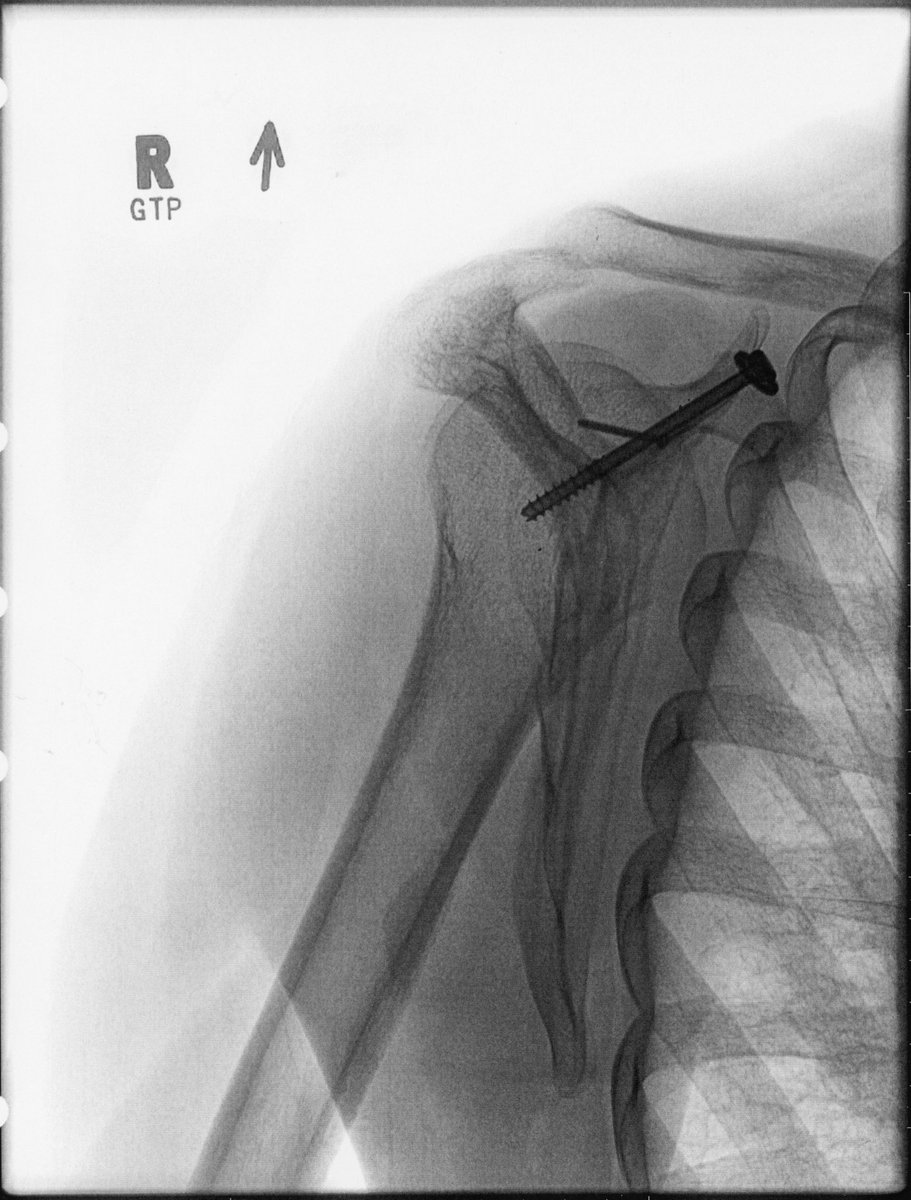

At the hospital I learned that I broke my pinky toe, my top right rib – which poked a hole in my lung – and my scapula, including the glenoid (which is the socket). Treatment wise, the lung required a chest tube to be inserted. And I’m told a glenoid break is quite rare.

That meant I had to switch hospitals to get the surgery. All told I was two weeks in hospital. I left after Easter with a screw in my shoulder. Surgery recovery is what has kept me away for two months as it’s been a slow rebuild. I’m healing 1% per day.